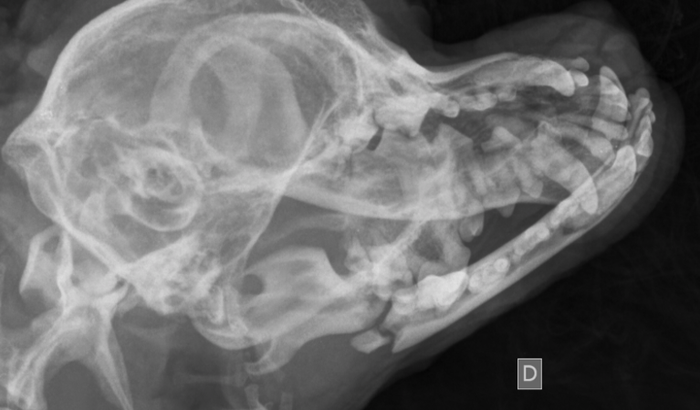

Meu nome é Leandro e sou o tutor de um animal de estimação que infelizmente sofreu um acidente e teve a mandíbula lesionada. É uma lesão grave que requer uma cirurgia urgente para corrigir o problema.

Desde que o acidente ocorreu, tenho buscado por opções acessíveis para realizar a cirurgia. Entrei em contato com várias faculdades da região, na esperança de encontrar uma solução mais econômica, mas infelizmente nenhuma delas oferece o procedimento a um preço que eu possa pagar.